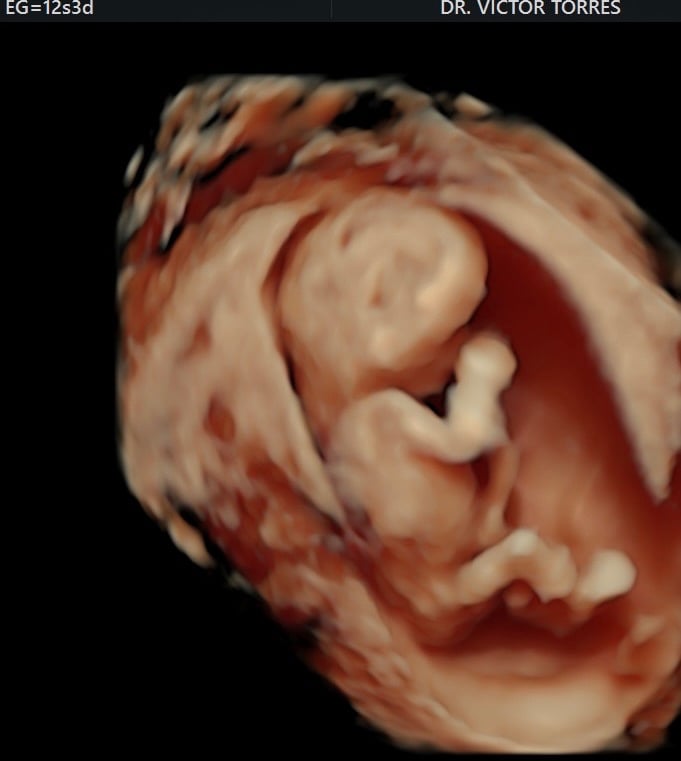

Monitoreo y cuidado especializado para el bienestar de tu bebé durante el embarazo.

Galería Neomamá

Explora momentos especiales y servicios para mamás y bebés aquí.